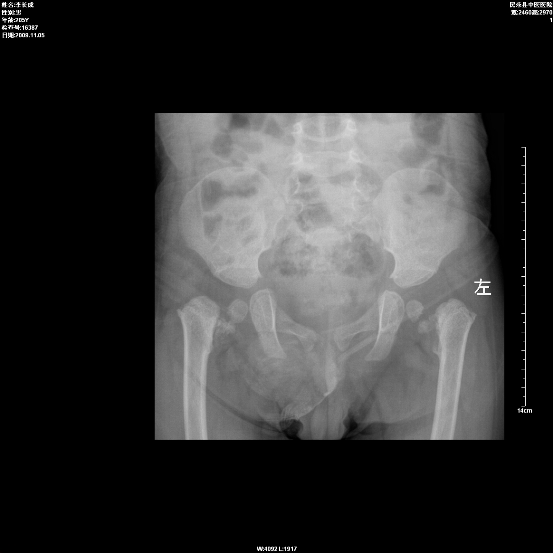

以下是引用zjzjr在2009-11-5 19:31:00的发言:[br]典型的先天性髋内翻,为股骨颈骨化障碍所致,x线表现为股骨颈缩短近于水平位,股骨颈与股骨干所成角<130度,股骨头位置相对下降,大粗隆位置相对上升.